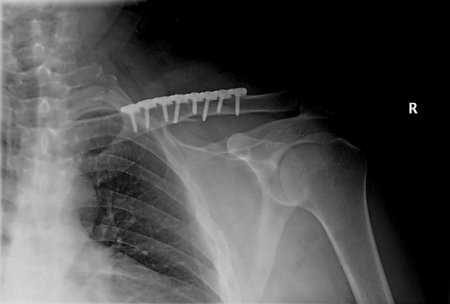

Титан имеет большую популярность в медицине: любят его ортопеды, кардиологи, стоматологи и даже нейрохирурги. Из титановых сплавов изготавливают легкие и долговечные хирургические инструменты.

В современном мире люди живут долгой активной жизнью. Но очень часто получают повреждения, например, в результате занятий спортом или в автомобильных авариях и происшествиях. И тут на помощь людям приходит металл будущего. Одним из ценных свойств титана является его биологическая совместимость с живой тканью. Титан и его сплавы (например, ВТ6 и ВТ14) является идеальным материалом для протезирования. Медики называют это свойство — «настоящее родство». Сочетание высокой удельной прочности и практически идеальной совместимости титана и его сплавов с тканями человеческого организма делает его максимально эффективным материалом для изготовления протезов, имплантантов, зубных металлокерамических коронок и каркасов мостовидных протезов. Титановые элементы совершенно безопасны для костей и мышц. Они не вызывают аллергию, не разрушаются при взаимодействии с жидкостями и тканями организма и, конечно, с медицинскими препаратами. Кроме этого, протезы, изготовленные из титановых сплавов, очень прочны и износоустойчивы, хотя все время выдерживают большие нагрузки.